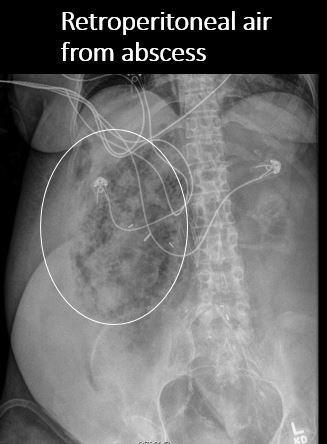

There is air in the retroperitoneum. [Yes/No]